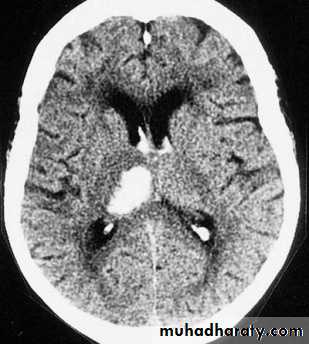

subarachnoid hemorrhage (SAH)

extravasations of blood into the subarachnoid space between the pial and arachnoid membranes80% are due to a ruptured berry aneurysm

Non contrast CT followed by CT angiography (CTA) of the brain can rule out SAH with greater than 99% sensitivity.

the principle imaging for ICH is CT scanning